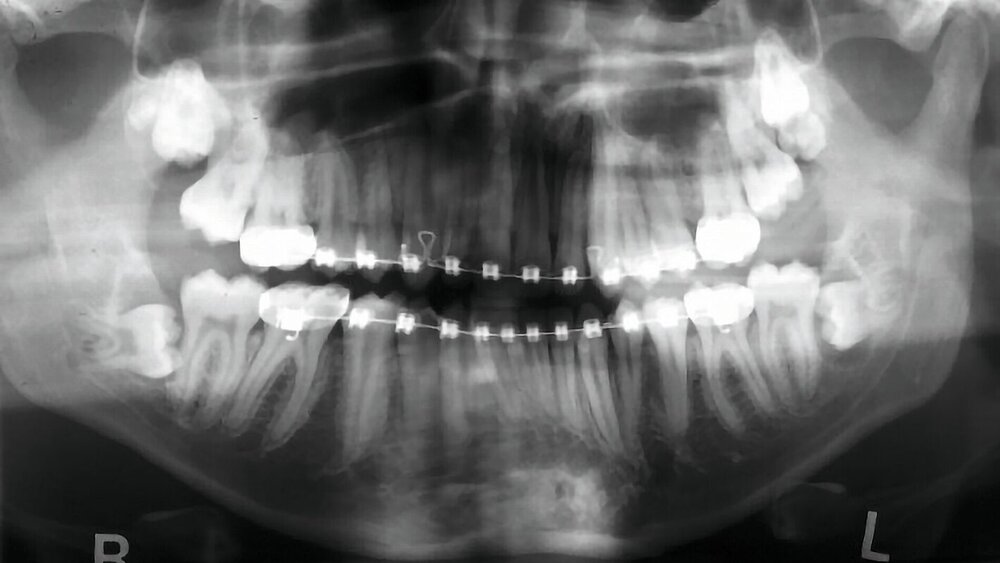

Neben der ausführlichen Anamnese und der klinischen Untersuchung ist eine röntgenologische Untersuchung wichtig. Zur Übersicht kann eine zweidimensionale Panoramaschichtaufnahme angefertigt werden, um die Lage und Angulation der Weisheitszähne sowie deren Beziehung zu ihren anatomischen Nachbarstrukturen beurteilen zu können [ARö/DGZMK, 2022; DGMKG, 2019].

Abbildung 1 zeigt ein Fallbeispiel einer Panoramaschichtaufnahme eines 18-jährigen Patienten mit den genannten röntgenologischen Anzeichen einer engen Lagebeziehung zum Nervkanal, zum einen in Regio 38, aber auch in Regio 48. Zudem befinden sich in Regio 18 und 28 unklare weitere zahnähnliche Strukturen.